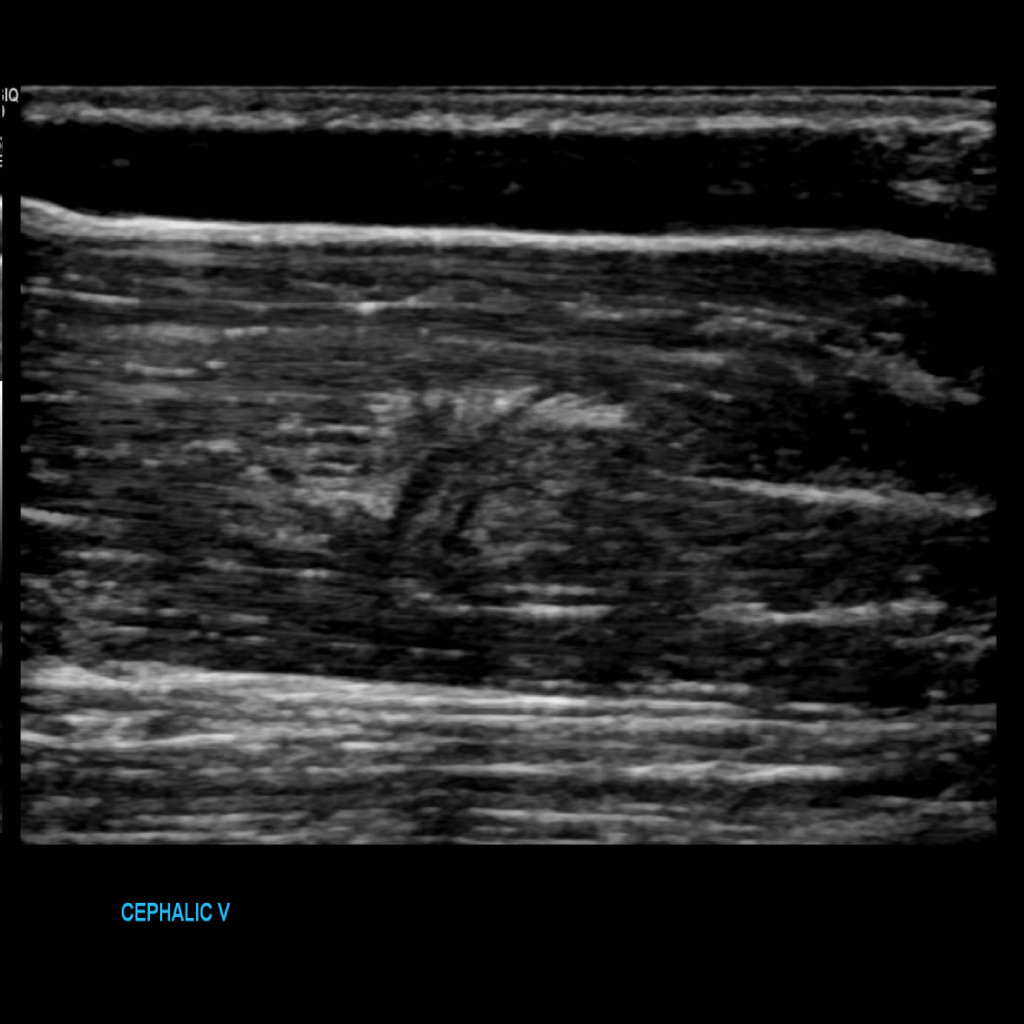

Scan the cephalic vein in grey scale, compression, color doppler and spectral doppler